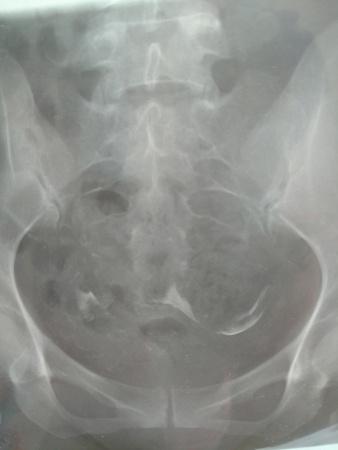

输卵管碘油造影的片子,请帮忙看看,医生意见不一致。

[attach]2075106[/attach]

一位认为输卵管通,但弥散不良,另一位认为通而且弥散也正常。请大家赐教。